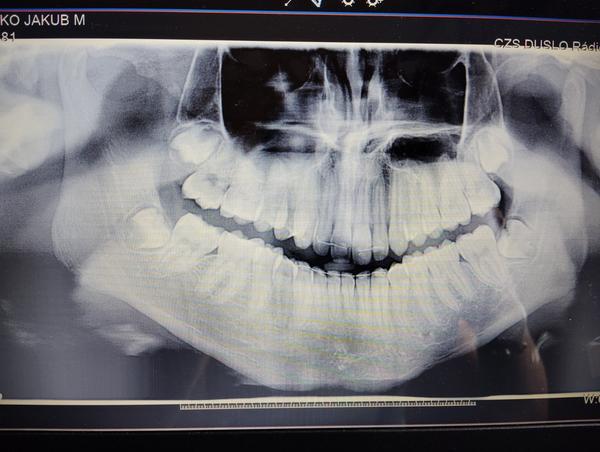

@mondolina ak je to len preto ze je ukončená orto liečba tak ma tam retiner ten to musí podržať. Naozaj nie je ani najmenší dôvod na vyberanie zubov a trápenie zbytočné. Ak teda nerobia problém ale podľa rtg absolútne nemajú prečo, tie horné sú dobré uložené, vyzerajú ze majú miesto, dolné tiez nie sú nijak veľmi zle.

@mondolina q prečo ich chcú vyberať? Ešte nemajú ukončený vývin, ten sa ukončí až po 18tom roku. Robia problem alebo len podľa rtg sa rozhodli?

píše tam, že je tam závažný priestorový deficit.

@mondolina vidim ale to absolútne nezodpovedá tomu co tam je. Šla by som sa poradiť k stomatochirurgovi ale ja by som určite nedala a hlavne ak reálne aj nič nerobia. On keď nenosí poctivo ten nočný tak sa mu posunu bez ohľadu na osmičky. A tie drôtik totadu drží stabilne ak sa neuvolni.